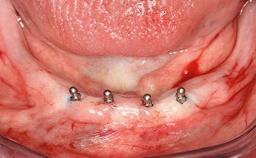

# of Implants 2

Type of Implants One-Piece

Defining Characteristics Fully edentulous lower jaw to be rehabilitated with two or more implants

Modality 2 interforaminal implants